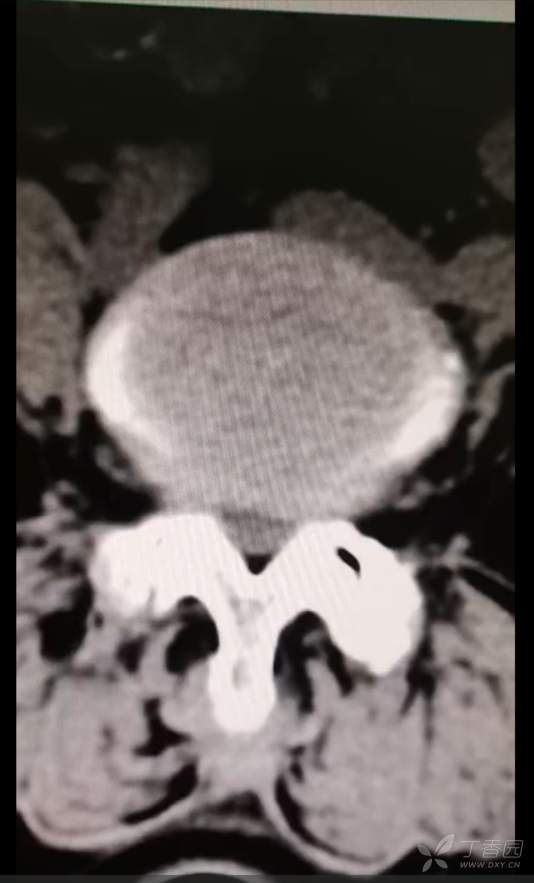

黄骨头脊柱内镜——腰4-5椎管狭窄侧路减压一例